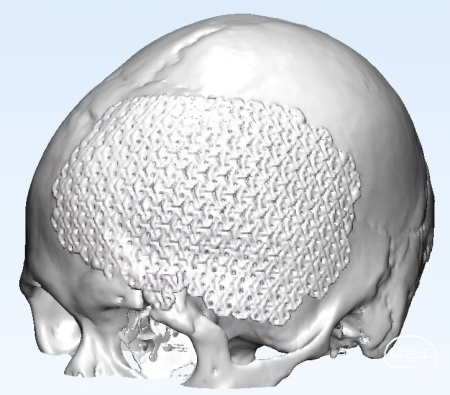

1. 去除钛网,重新行颅骨修补,修补材料为3D打印超高分子量聚乙烯(UHMWPE)网板。

2. 新修补材料植入颞肌下,嵌入骨窗内,恢复正常解剖层次,恢复容貌外观。

修补材料设计方案:UHMWPE网板,标准弧度设计,厚度4mm;与颅骨间隙0.8-1mm;预留孔颞部孔径4mm,其余3mm;采用全覆盖式,翼状结构固定。